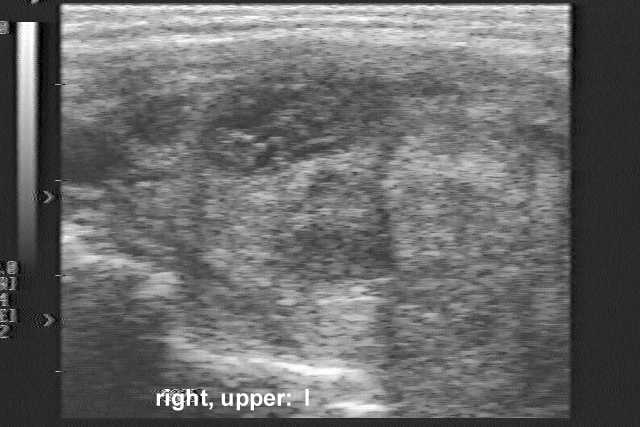

Palpation: The thyroid was moderately enlarged. A hard mass could be palpated in the right thyroid bed.

Ultrasonography revealed a hypoechogenic inhomogeneous nodule in the right lobe of the thyroid (the second US picture). The palpable mass was a hypoechoic lesion which was located just ventral to the right thyroid lobe.

Cytology from both lesions resulted in small cell malignant tumor. Based on nuclear molding we raised the possibility of small cell lung cancer, which was confirmed by immunocytochemistry: the tumor cells did not express LCA but gave a positive reaction for neuron-specific enolase.